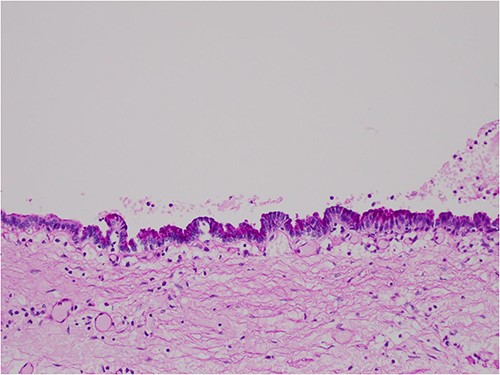

The histologic examination revealed numerous large, medium and small cysts separated by prominent stromal areas of fibrosis. These areas contained luminal eosinophilic concretions (Fig. 3). No ovarian-type parenchyma was found to suggest IPMN. The cyst formation maintained the outline of the native lobules, with some withered central islets appreciated. No papillary architecture was observed, and no epithelial dysplasia or invasive carcinoma was present. Epithelium lining the cysts was attenuated in some areas, and cuboidal in others. Where the epithelium was recognizably cuboidal, there was scattered acinar differentiation noted, characterized by apical cytoplasmic granules positive on periodic acid-Schiff-diastase (PASD) staining (Fig. 4). Acinar differentiation did not therefore have to be confirmed with further immunohistochemistry.

Hematoxylin and Eosin (H&E) × 40 showing benign cysts and luminal eosinophilic concretions.